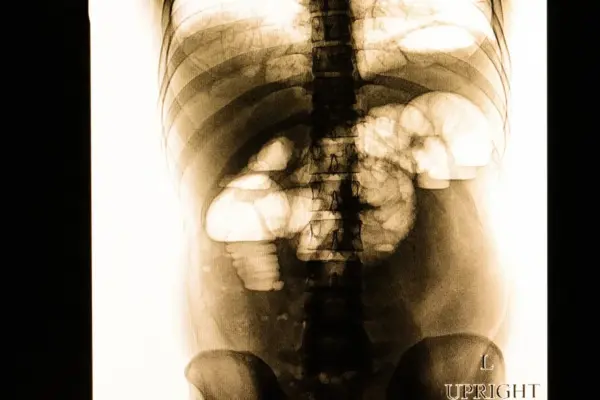

Ειλεόσ: Τι συνέβη με τον ειλεό της Μαρέβας Γκραμπόφσκι – Μητσοτάκη;

Η Μαρέβα Γκραμπόφσκι – Μητσοτάκη διαγνώστηκε με αποφρακτικό ειλεό και υπεβλήθη σε λαπαροτομία. Η κατάσταση της υγείας της παρακολουθείται στενά.